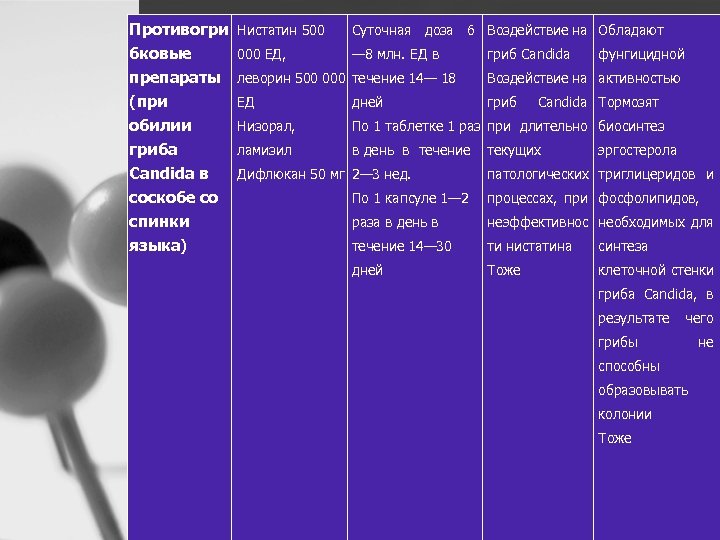

Противогри Нистатин 500 бковые 000 ЕД, препараты (при обилии гриба Candida в соскобе со спинки языка) Суточная доза 6 Воздействие на Обладают — 8 млн. ЕД в гриб Candida фунгицидной леворин 500 000 течение 14— 18 Воздействие на активностью ЕД дней гриб Низорал, По 1 таблетке 1 раз при длительно биосинтез ламизил в день в течение текущих Дифлюкан 50 мг 2— 3 нед. Candida Тормозят эргостерола патологических триглицеридов и По 1 капсуле 1— 2 процессах, при фосфолипидов, раза в день в неэффективнос необходимых для течение 14— 30 ти нистатина синтеза дней Тоже клеточной стенки гриба Candida, в результате чего грибы способны образовывать колонии Тоже не